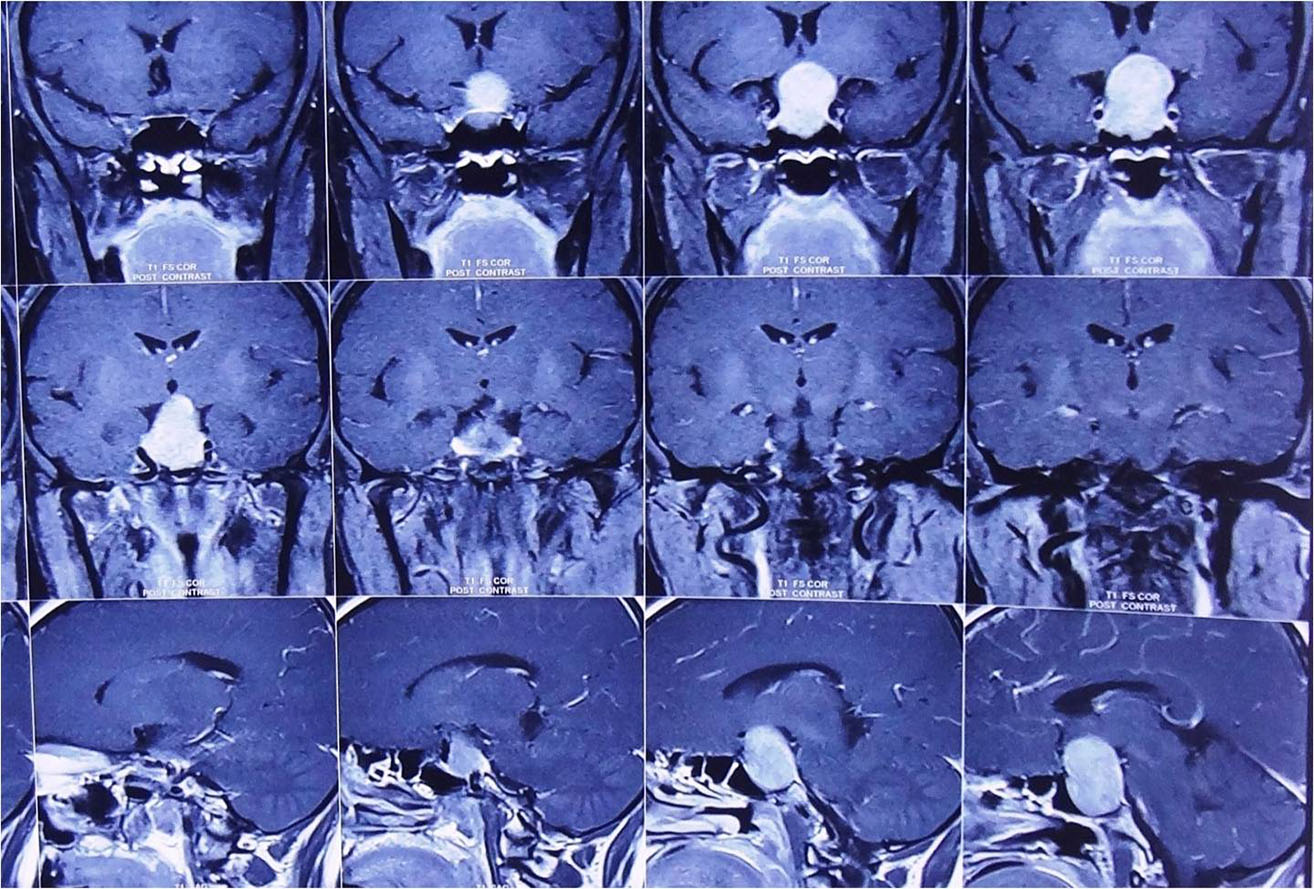

any of these symptoms he/ she should consult a neurosurgeon immediately. Usually CT Scan/ MRI of brain help

in the diagnosis. Most of the brain tumours can be safely treated by surgery but the treatment plan may vary